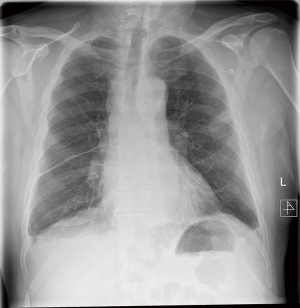

We describe a rare case of a postoperative mediastinal bleeding that occurred in our service related to coagulopathy disorder (Figures 1,2).

This 66-year-old man initially presented with haemoptysis and was found to have a left upper lobe lesion on computed tomography (CT). Positron emission tomography (PET) scan revealed a nodule with an SUVmax of 6.9 in the left upper lobe and hilar and paratracheal lymph nodes with SUVmax of 4.1 and 3.1 respectively, all suspicious for primary lung cancer. He was referred for mediastinoscopy for staging and diagnosis purposes. Past medical history included being an ex-smoker, myelofibrosis on medical treatment, chronic obstructive pulmonary disease (COPD), hypertension and gastro-oesophageal reflux. Preoperative haematological advice was to continue his medications. He underwent a cervical videomediastinoscopy, which was routine and uneventful. Stations 2R, 2L, 4R, 4L and 7 were sampled. There was minimal expected bleeding experienced when the biopsies were taken and haemostasis was achieved prior to closure. He was discharged home the same day.

Later that evening he re-presented with upper abdominal pain. Investigations revealed abnormal clotting with a slightly raised partial thromboplastin time (PTT) and activated partial thromboplastin time (aPTT), a raised white cell count and haemoglobin that had decreased by 10 g/L from pre-operatively. Chest X-ray showed a slightly widened mediastinum. A CT scan showed a mediastinal haematoma predominantly in the subcarinal region, extending inferiorly to the oesophageal hiatus and superiorly around the carina and distal trachea, along with bilateral pleural effusions, right larger than left. Aortic and bronchial angiogram did not demonstrate a bleeding point, and also found that anyway the bronchial arteries were very small and not easily amenable to embolization. Haematological advice this time supported the impression of coagulopathy due to myelofibrosis, replacement of coagulation factors was prescribed.